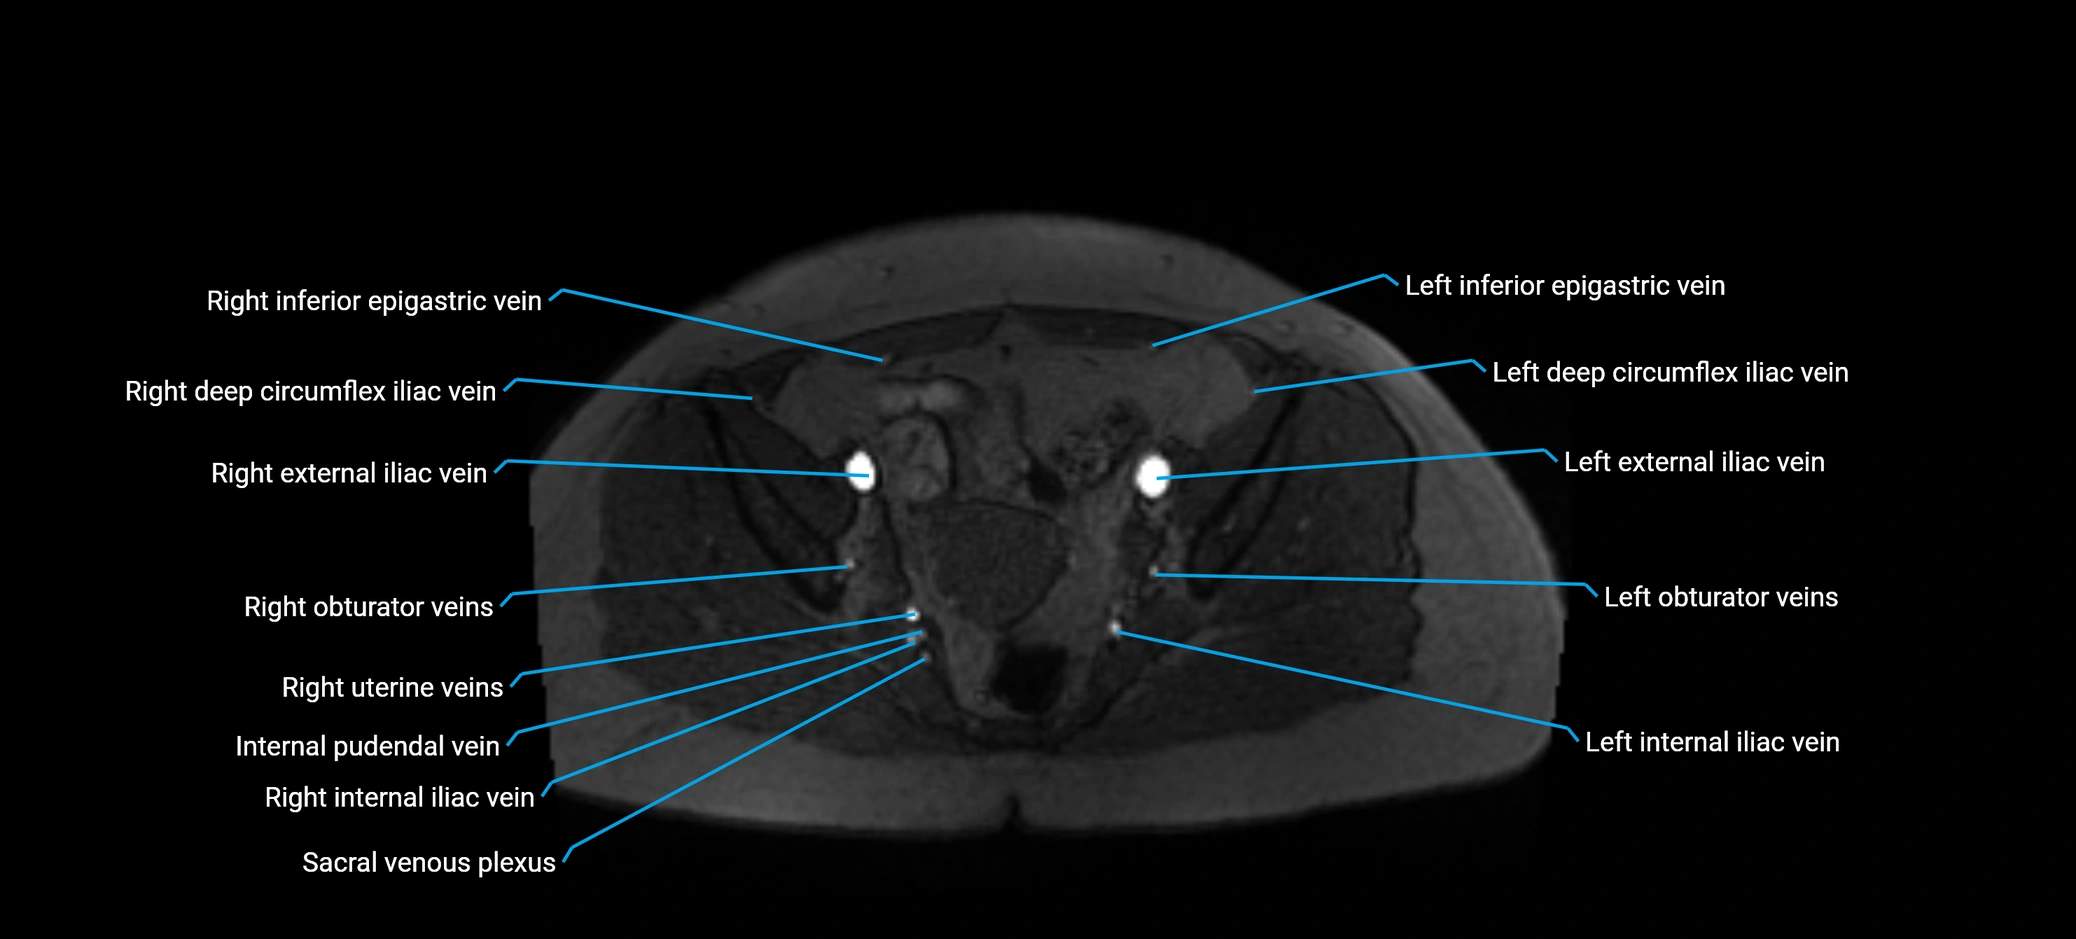

MRI image

image